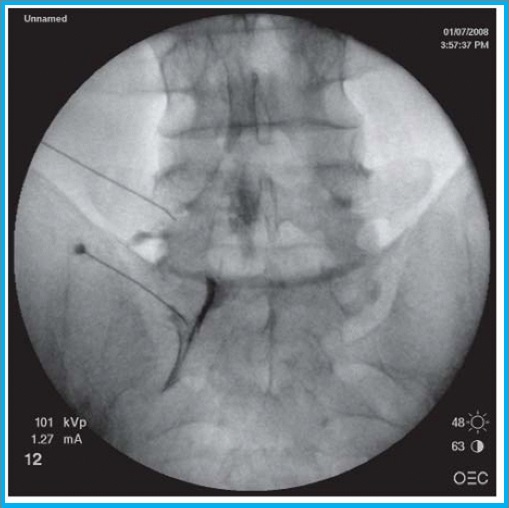

Τι είναι η Διατρηματική επισκληρίδιος έγχυση

Στην διατρηματική έγχυση, υπό ακτινοσκοπική καθοδήγηση, το φαρμακευτικό διάλυμα χορηγείται απευθείας στο σημείο εξόδου της νευρικής ρίζας, για την αντιμετώπιση του ριζιτικού άλγους.